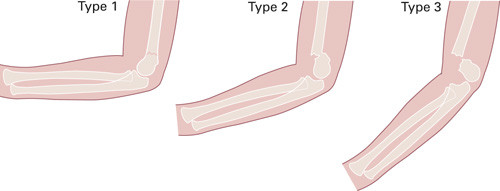

Perkutan pinneteknikk ble beskrevet første gang av Judet i 1947 (19), og er den dominerende behandlingsmetoden i verden i dag (14, 20) – (22). Bruddet reponeres lukket og fikseres med Kirschner-pinner som føres inn perkutant. Pinnene settes enten i kryss fra hver kondyl og opp i diafysen, eller kun fra lateralsiden. I tillegg immobiliseres bruddet i gips. I Skandinavia har man hatt lang tradisjon for både strekkbehandling og perkutan pinneteknikk (10, 23). Fordelen med perkutan pinning sammenliknet med immobilisering i gips alene er bedre kontroll over bruddfragmentene, og dermed bedre reposisjon uten å måtte immobilisere albuen så flektert at faren øker for kompartmentsyndrom i anteriore fossa med risiko for påfølgende Volkmanns kontraktur (24). Det er vist at at perkutan pinning er billigere enn strekkbehandling pga. kortere liggetid i sykehus, og at behandingsmetoden gir lavere risiko for varusfeilstilling (21). Ulempene ved metoden er hovedsakelig pinneinfeksjon og risiko for iatrogen skade av nevrovaskulære strukturer, hovedsakelig n. ulnaris ved bruk av medial pinne (25). Dyp infeksjon er meget sjeldent, og forekommer i under 0,2 % av tilfellene (26). Antibiotikaprofylakse i forbindelse med operasjonen er derfor ansett som unødvendig og blir ikke gitt rutinemessig (26).

Det er uenighet i litteraturen om den optimale pinneplasseringen. En kadaverstudie fra 1994 utført av Zionts og medarbeidere viste at kryssende pinner er mer biomekanisk stabile enn to laterale pinner (27), men man har ikke kunnet påvise klinisk konsekvens av dette (20, 22, 28). Hovedargumentet mot kryssende pinner er risiko for skade på n. ulnaris (29). Komplette utfall av n. ulnaris forekommer sjelden, og skyldes som regel skade på nerven i forbindelse med frakturen eller reposisjonen. Mindre alvorlige utfall/nevrapraksi går som regel tilbake etter fjerning av pinnen (26, 30). En metaanalyse fra 2007 konkluderte med at valg av pinnekonfigurasjon betyr lite for komplikasjonsrisikoen og kan derfor være opp til den enkelte kirurg (25). På Akershus universitetssykehus har vi som rutine å bruke kryssede pinner. Det er uklart hvor mange pinner som er nødvendig (31). I de fleste studier har man benyttet to pinner som standard, og latt kirurgen vurdere behovet for flere pinner peroperativt. I et retrospektivt materiale på 112 brudd fra Akershus universitetssykehus var 67 % operert med to kryssede pinner, 26 % med tre pinner (to laterale og en medial) og 5 % med fire pinner (to laterale og to mediale) (5).